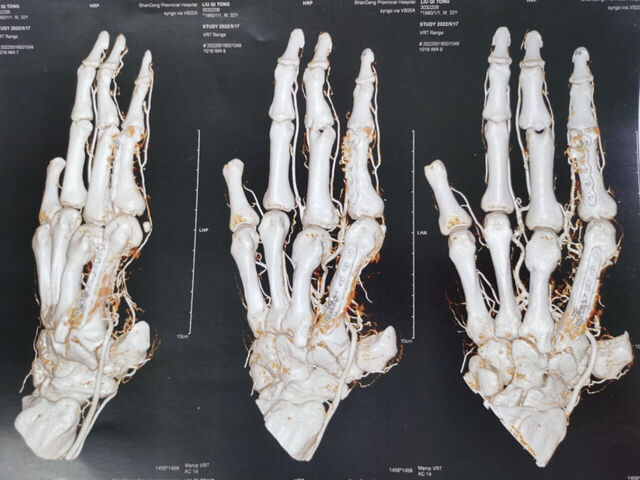

示指长手指再造。术后1年随访

微信图片_20230921213851.jpg 微信图片_20230921213905.jpg 微信图片_20230921213916.jpg 微信图片_20230921214427.jpg 微信图片_20230909224030.jpg 微信图片_20230909224014.jpg 微信图片_20230909224025.jpg 微信图片_20230909224007.jpg 微信图片_20230909224002.jpg 微信图片_20230909223945.jpg 微信图片_20230909224010.jpg 微信图片_20230909224018.jpg

微信图片_20230909224022.jpg